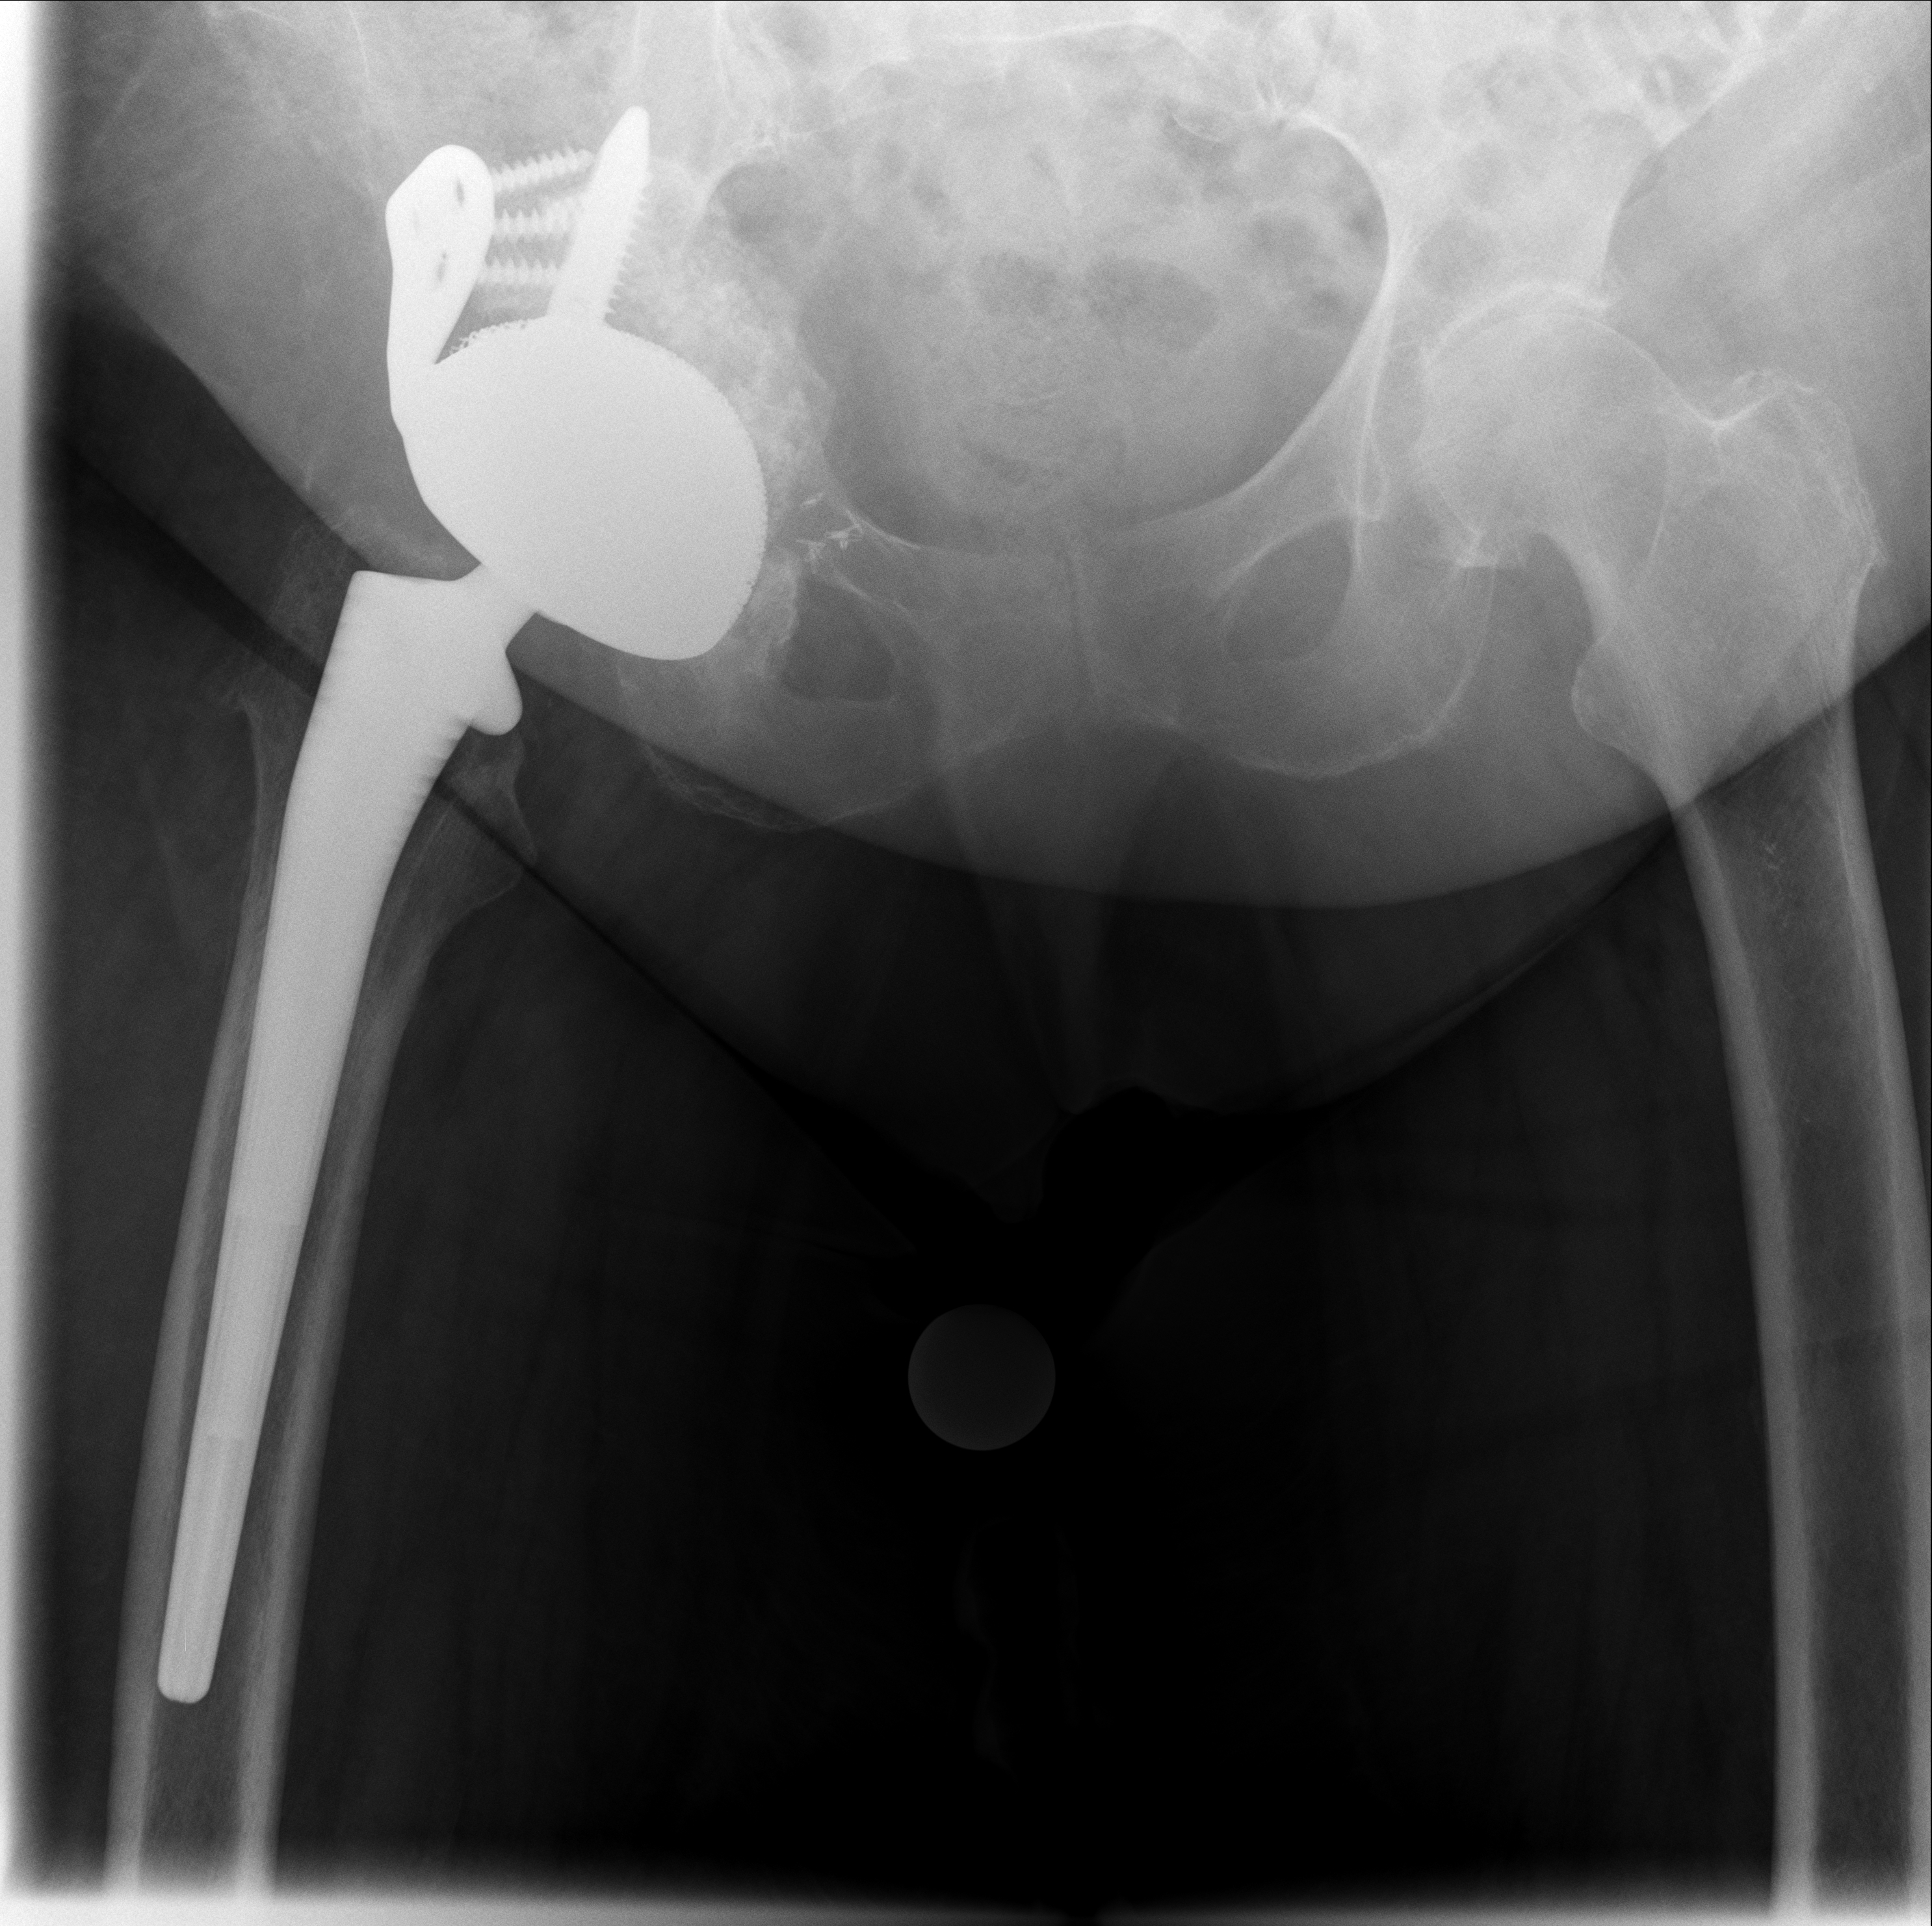

Röntgenbilder im Verlauf: korrekte Lage → Luxation → neue TEP nach Wiedereinbau

24.02.2026 - Neue TEP

Röntgen Februar 2026

Neue Hüft-TEP rechts nach Wiedereinbau

24.02.2026 - Neue TEP!

Becken 2026

24.02.2026 - Postoperativ

Röntgen Becken + Hüfte rechts (Kontrolle nach Wiedereinbau)

3 Aufnahmen | Becken tief + 2x Hüfte Lauenstein | 5 Tage nach OP

24. Februar 2026

Postoperative Röntgenkontrolle

Röntgen Becken tief + 2x Hüfte Lauenstein R – Kontrolle 5 Tage nach Wiedereinbau.

24.02.2026 - POSTOP

Röntgen Becken tief (nach Wiedereinbau)

DICOM

Kontrolle Becken 5 Tage nach Wiedereinbau TEP